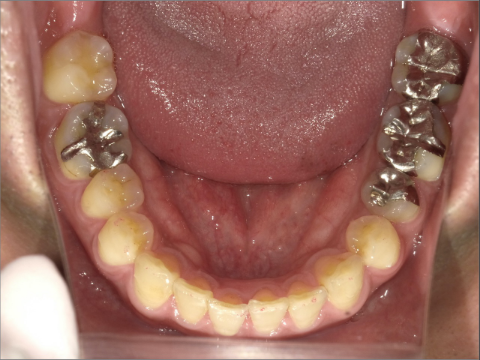

ご年齢 35歳男性 治療期間 2022/08/22〜2023/03/24(1年5ヶ月)

診断 110,000円(税込) アライナー 550,000円(税込) リテーナー 55,000円(税込)

ご年齢 35歳男性

治療期間 2022/08/22〜2023/03/24(1年5ヶ月)

診断 110,000円(税込)

アライナー 550,000円(税込)

リテーナー 55,000円(税込)

BEFORE

AFTER